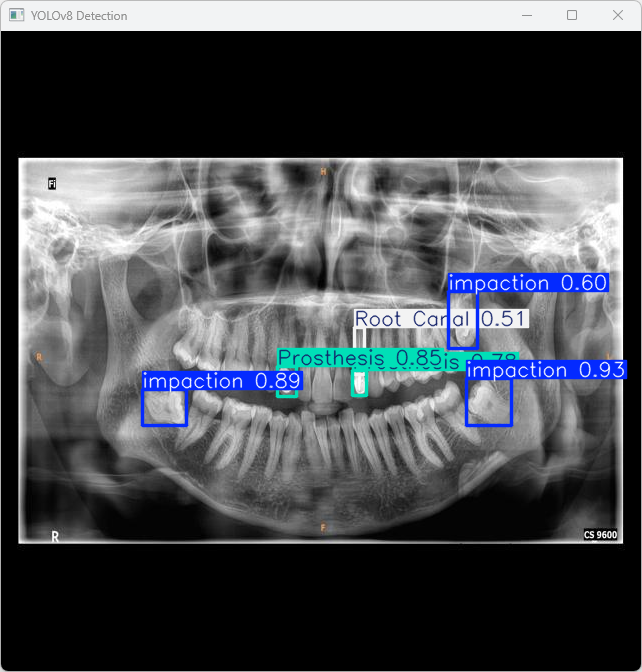

执行imgTest.py代码后,会将执行的结果直接标注在图片上,结果如下:

这段输出是基于YOLOv8模型对图片“imagetest.jpg”进行检测的结果,具体内容如下:

图像信息:

(1)处理的图像路径为:TestFiles/imagetest.jpg。

(2)图像尺寸为 640×640 像素。

检测结果:

(1)检测到 3 个阻生牙(Impaction)

(2)检测到 1 个根管治疗(Root Canal)

(3)检测到 2 个修复体(Prosthesis)

处理速度:

(1)预处理时间: 2.999 毫秒

(2)推理时间: 5.028 毫秒

(3)后处理时间: 49.869 毫秒

在该图像中,YOLOv8模型检测到了 3 个阻生牙、1 个根管治疗和 2 个修复体的目标,整个检测过程包括预处理、推理和后处理,总计花费约57.9毫秒,结果保存至 runs\detect\predict 目录。